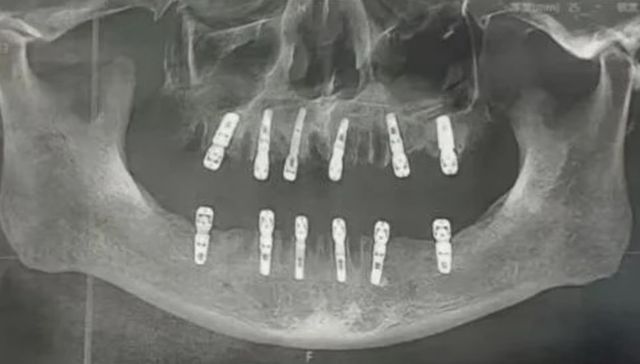

En un día le sacaron 23 dientes y le hicieron 12 implantes. Murió